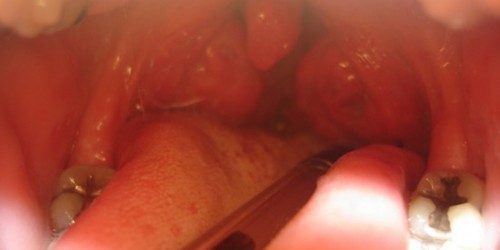

I need information about retropharyngeal absess patophysiology. My 8 years old son often has problems with sore throat and cough. He takes antibiotics and I am worried because of amount of medicines he has to use.

Retropharyngeal absess is usually complication of an acute tonsillitis. Any of microorganisms that may cause tonsillitis may be the causative agent of RA. Most commonly staphs, haemophilus and pneumococci are found in specimen. It can be represented in mononucleosis. RA is also documented without any prior history of tonsillitis. Antibiotic therapy is recommended.